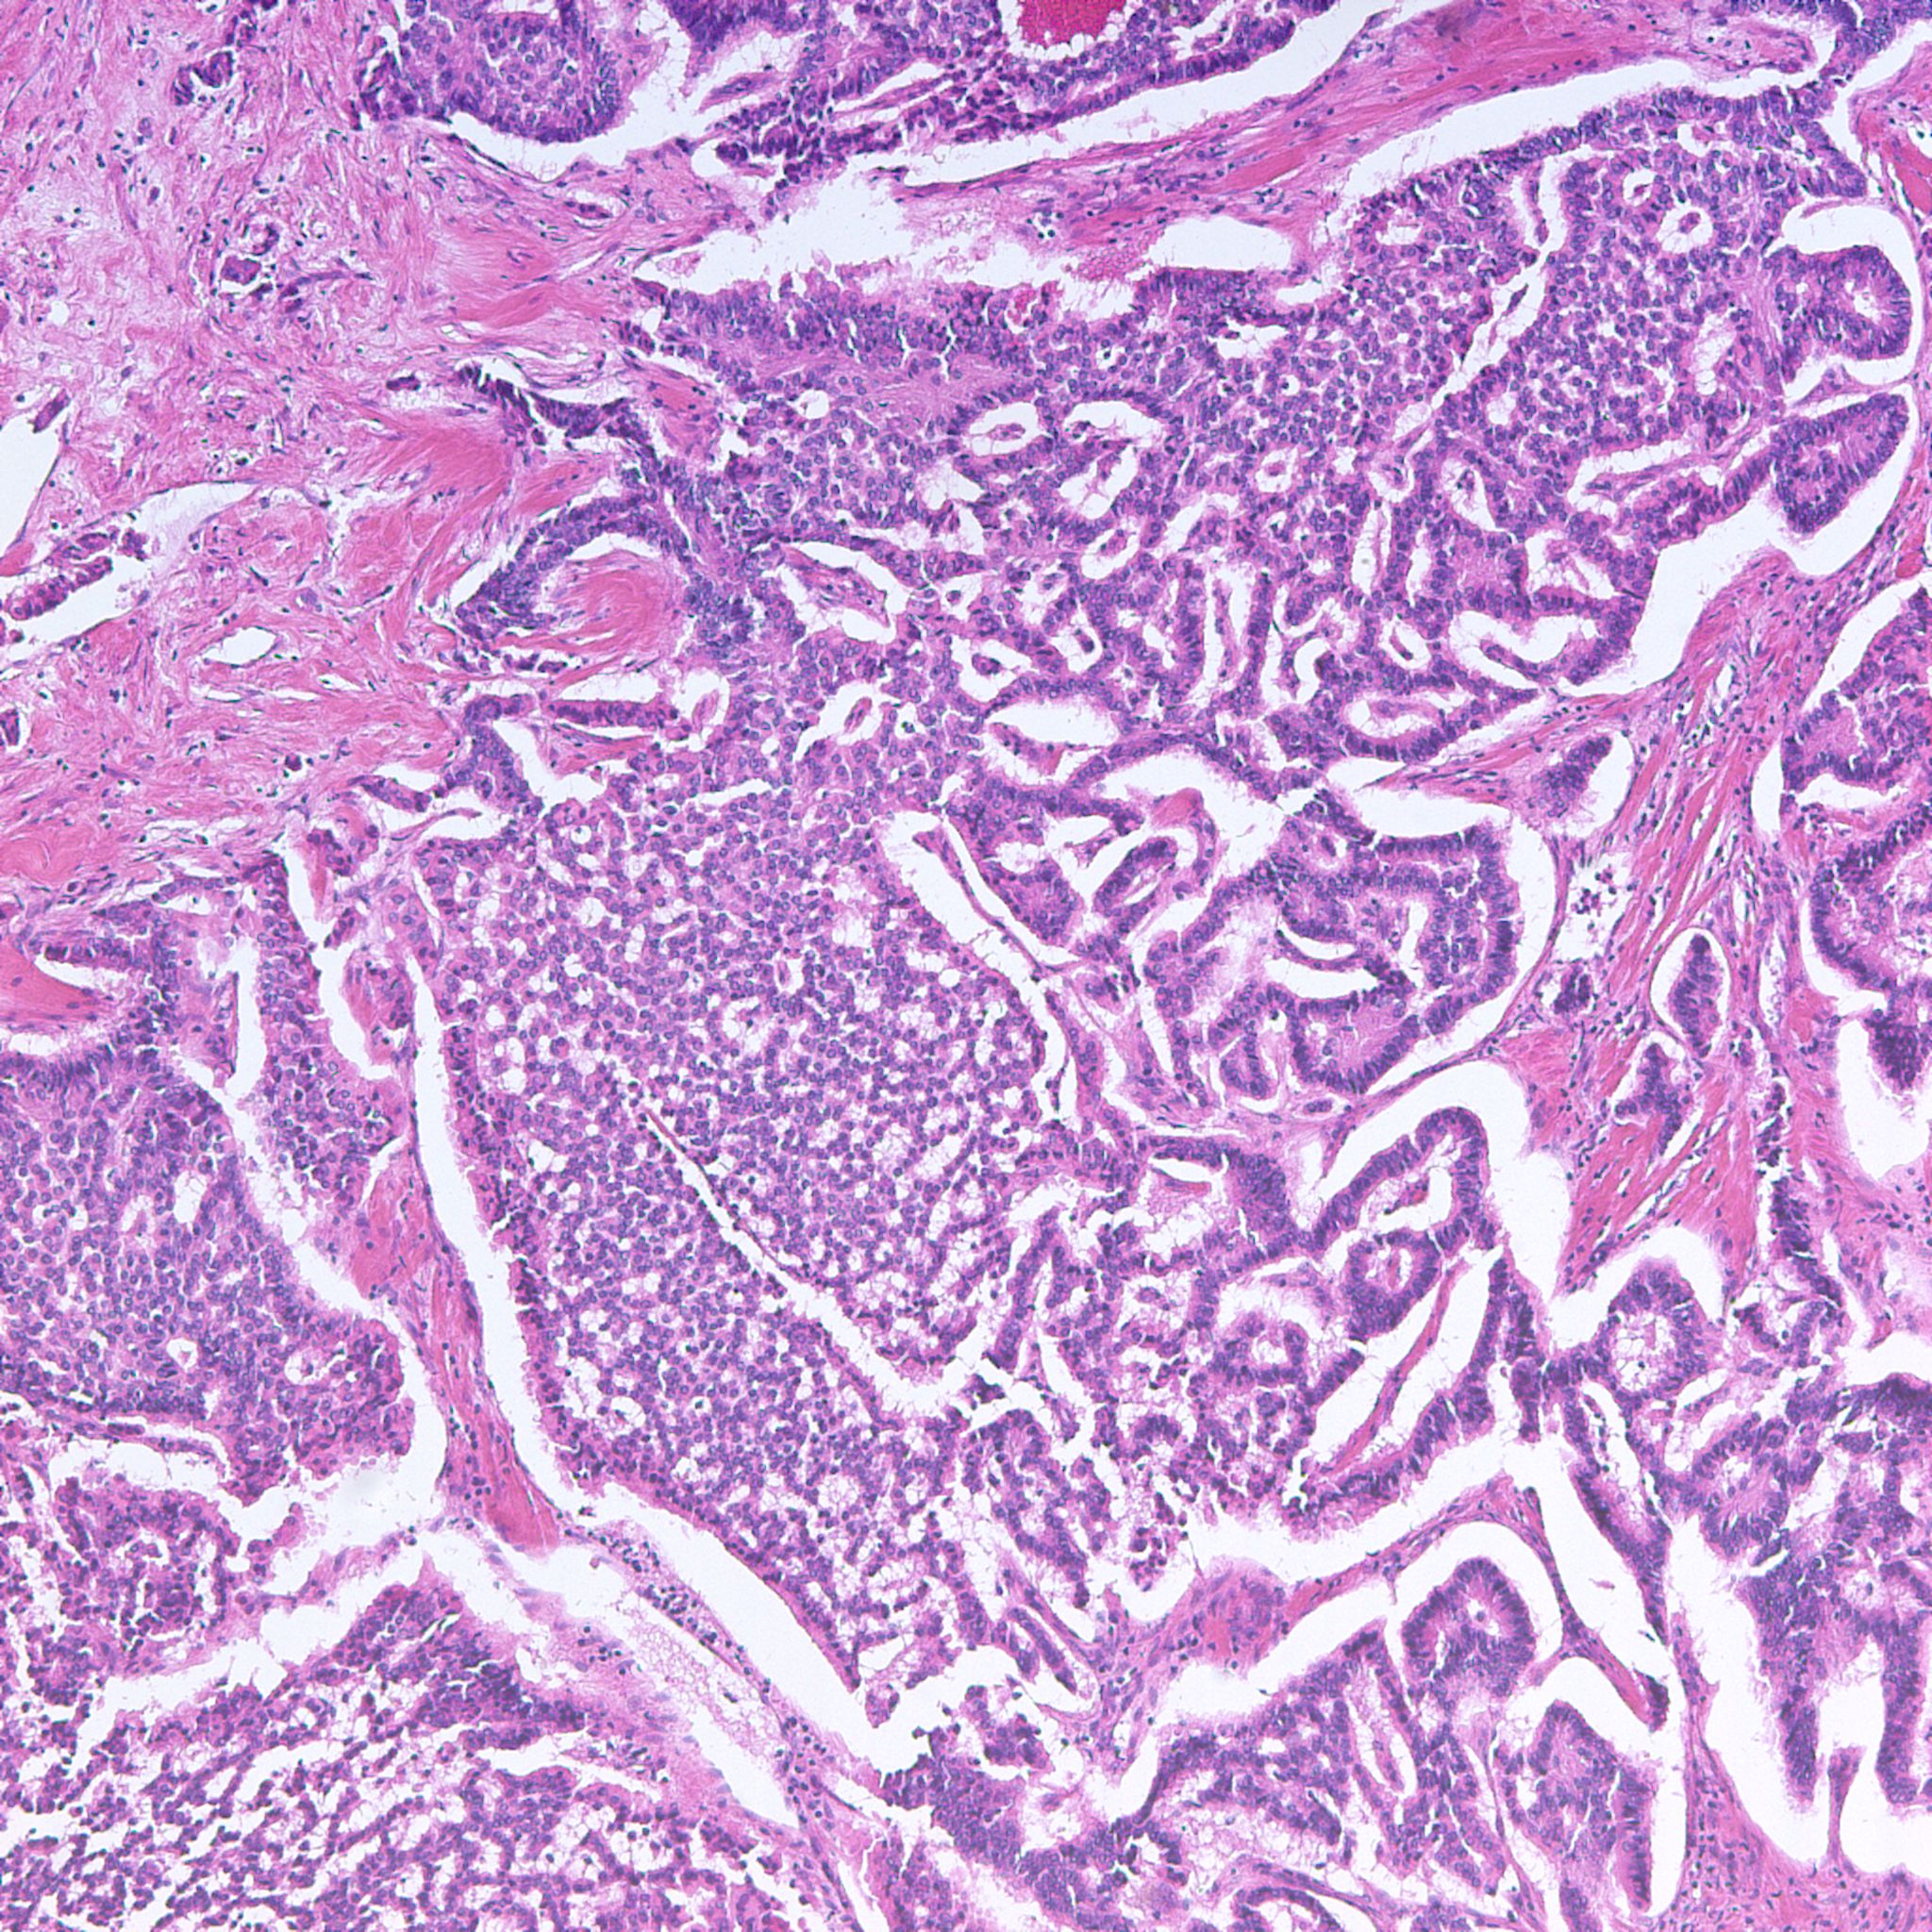

Classification of renal tumors

Case ID: 1230